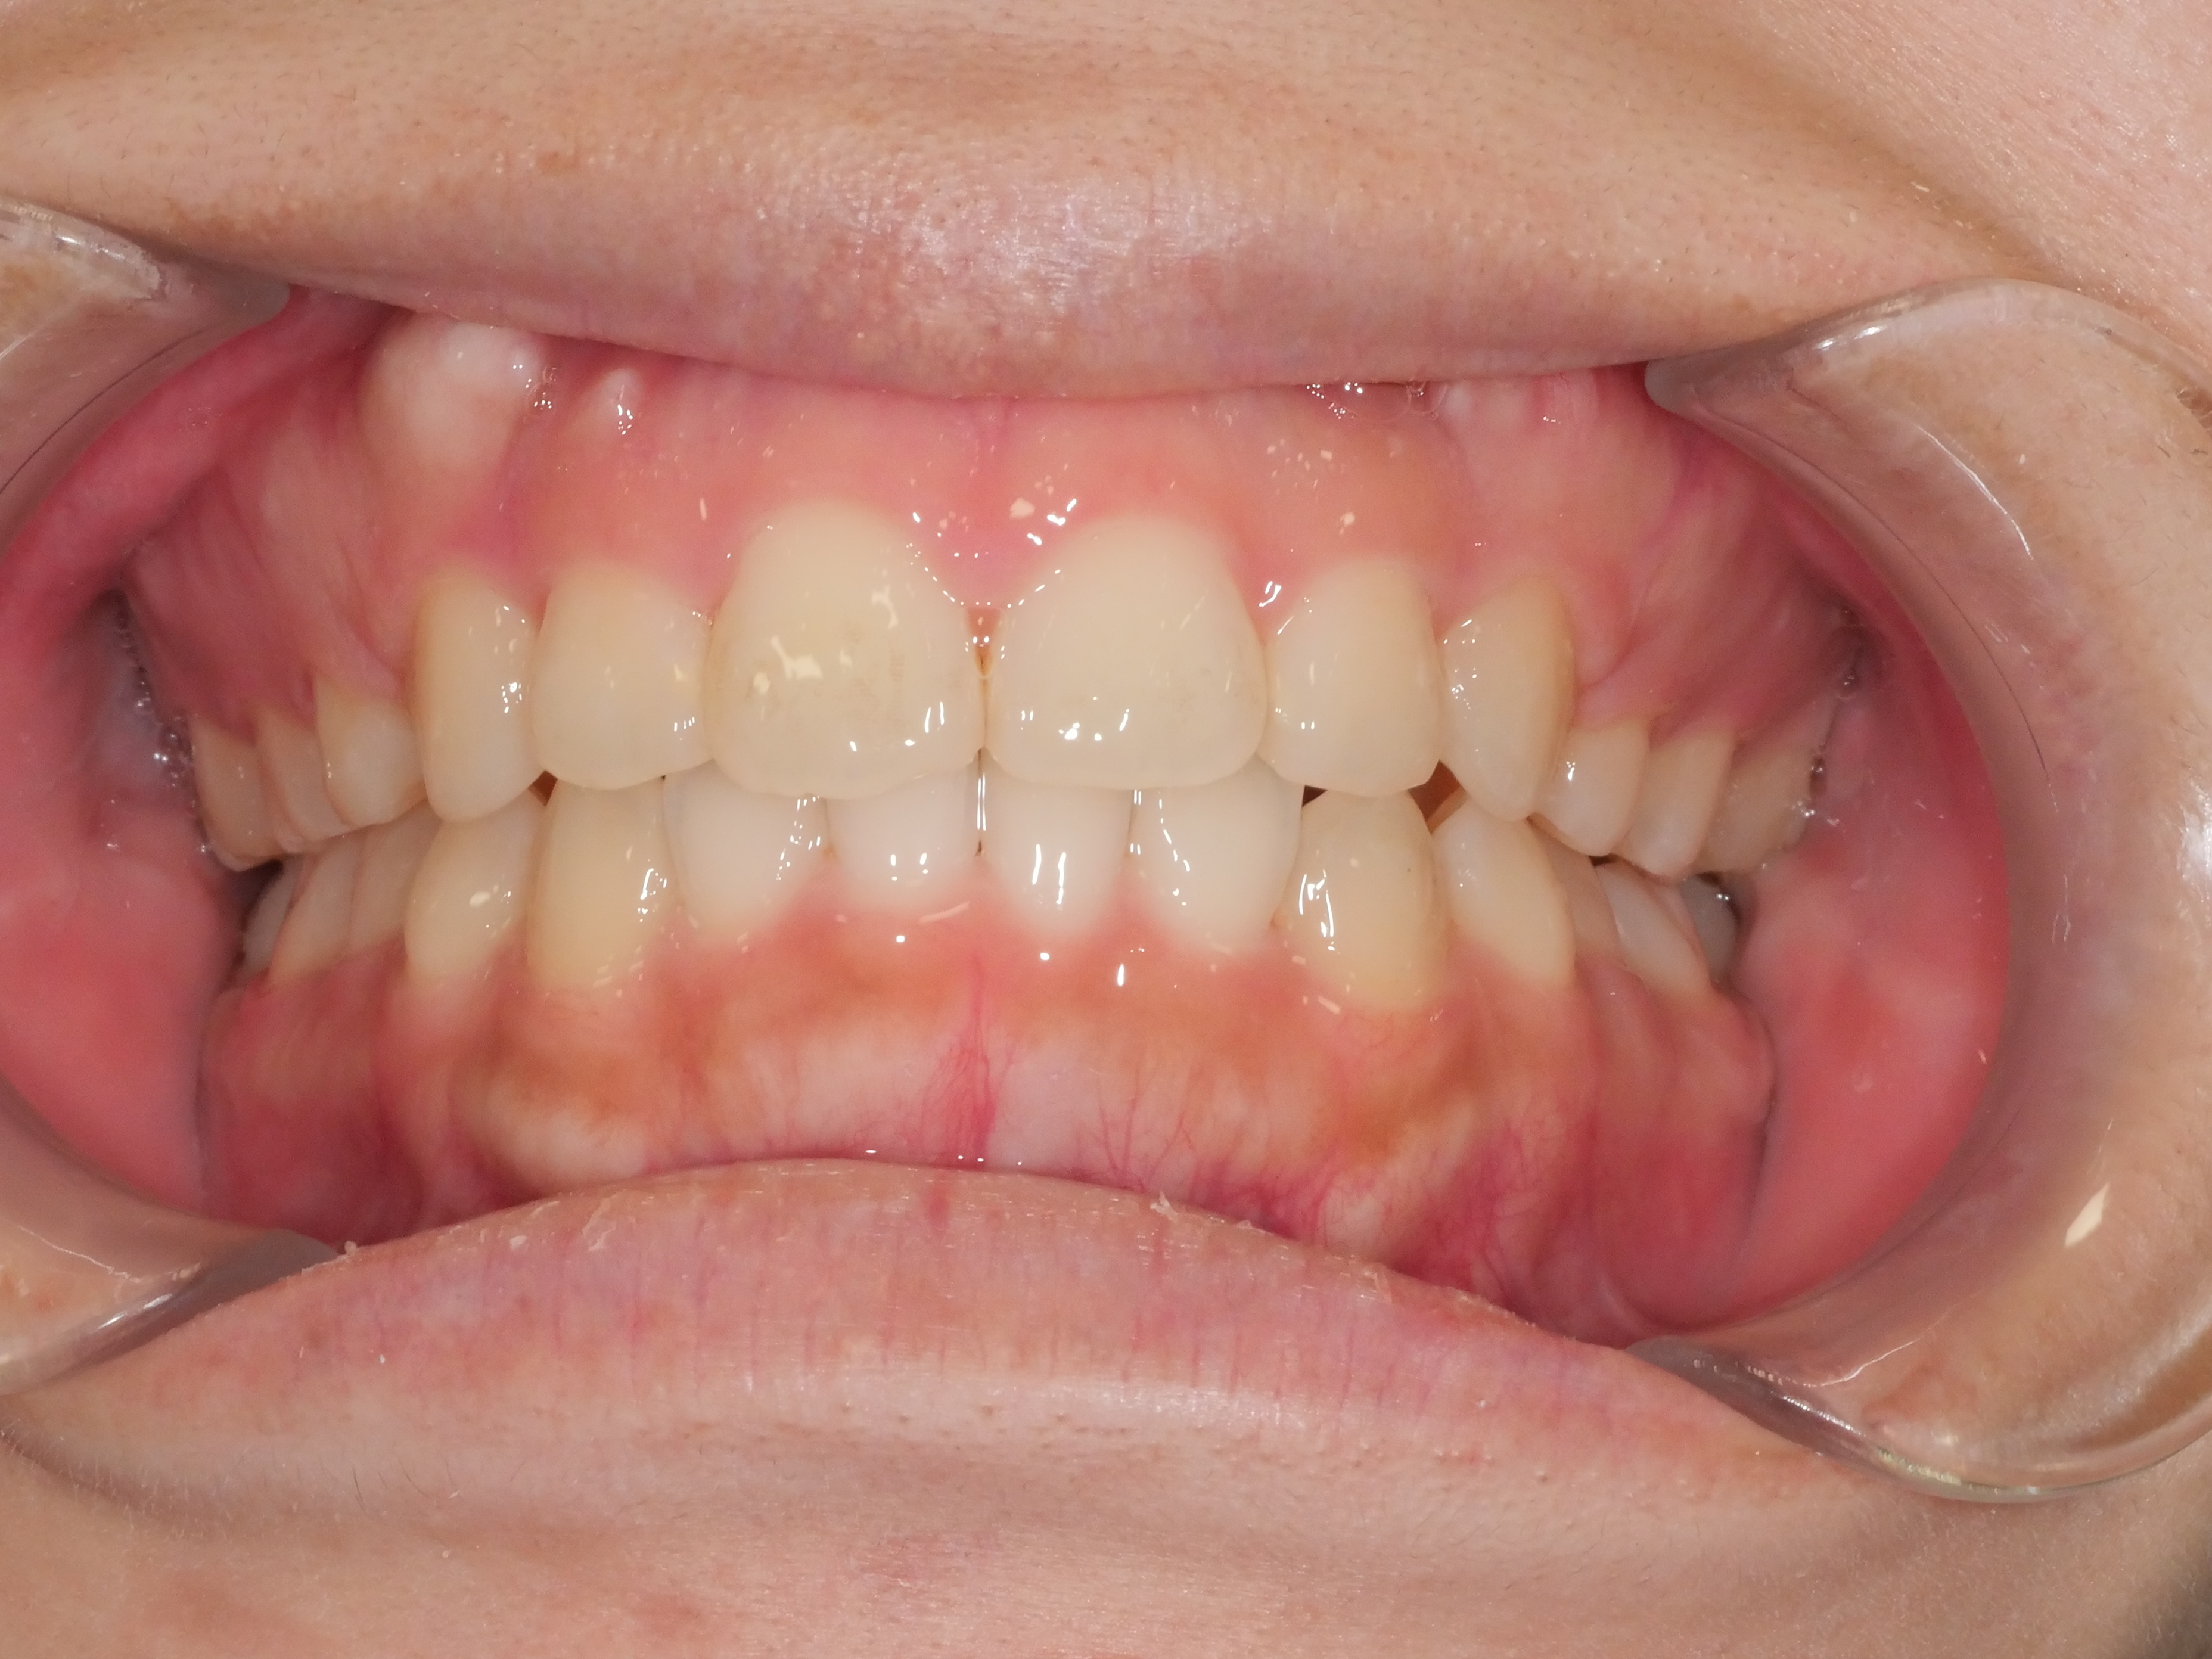

出っ歯を治したい

年齢層 20代

性別 女性

主訴 【主訴】出っ歯を治したい 【診断・症状】上下凸凹、開咬、口元が出てる

治療費用 検査・診断:38,500-/裏側矯正治療:1,397,000-(※全て税込)

治療期間 約2年(26回)

抜歯 有(上4,4)

矯正の装置 裏側矯正(舌側矯正)

副作用、リスク 歯肉退縮,歯根吸収,疼痛,咬合の違和感,装置の違和感,虫歯,歯肉炎

case14_出っ歯_before

Before